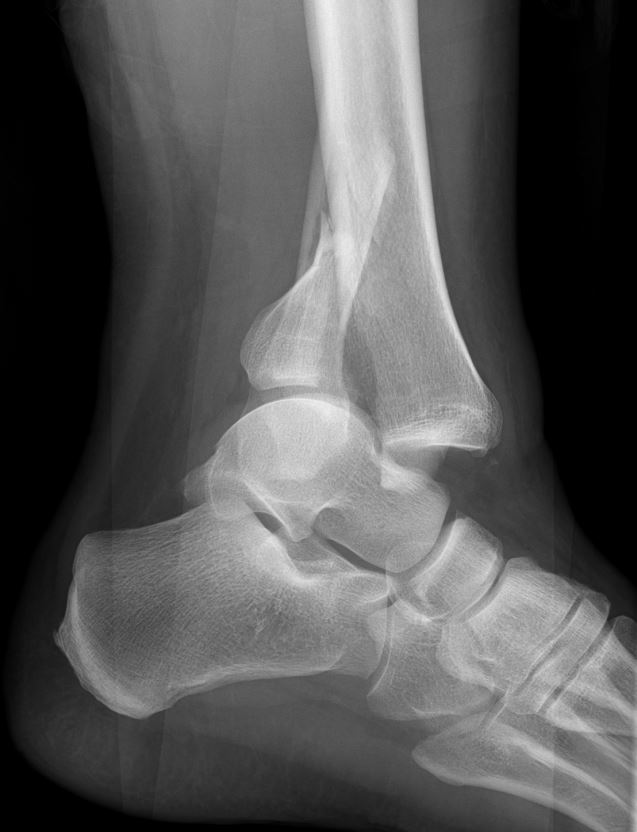

Home Schwerpunkte Krankheitsbilder Sprunggelenk-Fraktur Pilon Luxatiosnfraktur röntgen setilich vor OP

Pilon Luxatiosnfraktur röntgen setilich vor OP

Luxationsffrkatur oberes Sprunggelenk im Röntgen